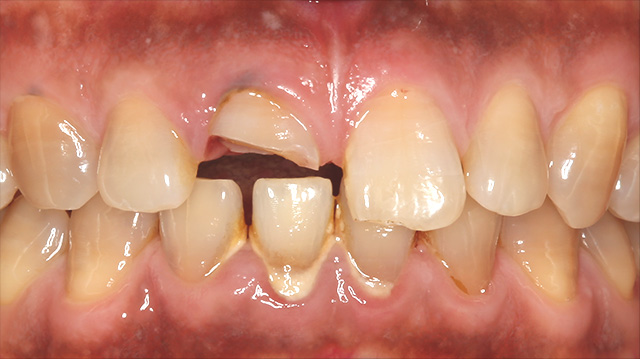

| 主訴 | 転倒して歯が割れた |

| 治療回数 | 3回 |

| 治療期間 | 約1ヶ月 |

| 費用 | 仮歯 5,500円 ジルコニアクラウン 176,000円 |